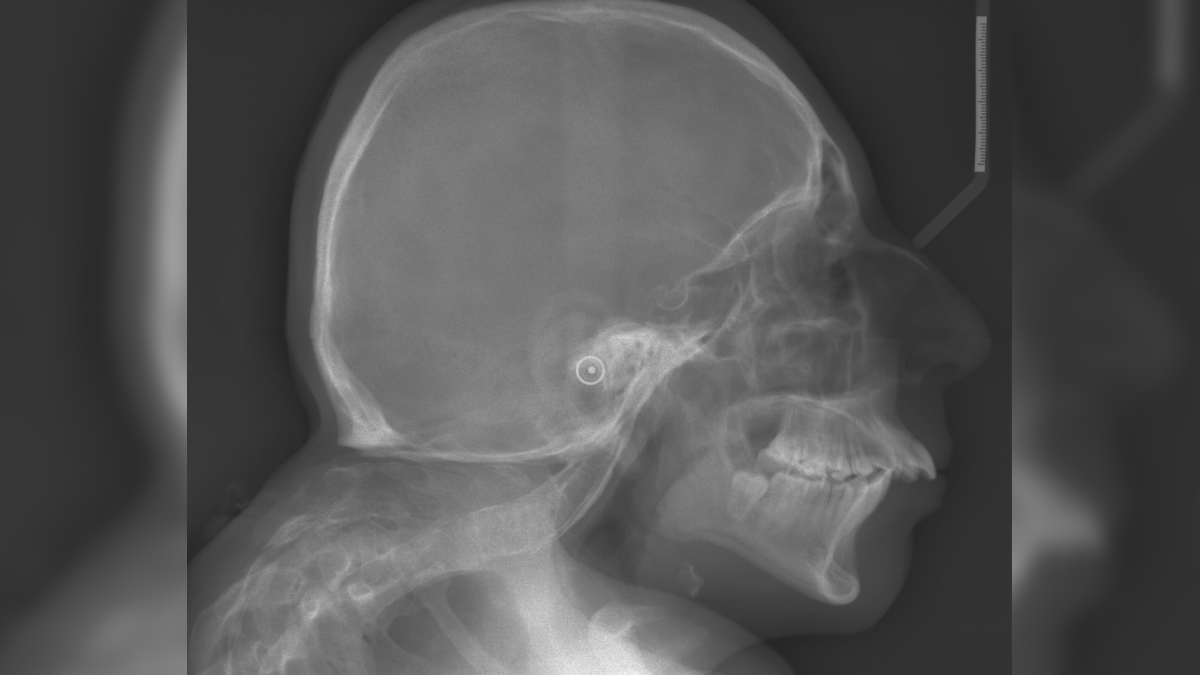

Dr Abhishek Mannem, Spine Surgeon and Medical Director, Bangalore Hospitals, Bangalore, explains, “Klippel-Feil Syndrome is a rare congenital condition where two or more neck vertebrae are abnormally fused together. This fusion happens during fetal development, not after birth.” He adds, “The classic signs of KFS are a short neck, limited neck movement, and a low hairline at the back. These symptoms are often called the ‘classic triad’ of KFS.”

Dr Mannem further explains that this fusion occurs because the neck bones do not separate like they should when a baby is growing in the womb. “The exact cause can be different for each person, but scientists have found that changes in certain genes, such as GDF6, GDF3, and MEOX1, can play a role,” he says.

According to the expert, in people with KFS, the bones in the neck, called vertebrae, do not separate properly during early development. Instead, they stay joined together, which is known as congenital fusion. This can change the shape of the neck and affect how the spine lines up. Because the neck cannot move as freely, people with KFS might find it hard to turn their head or look up and down.

A study published in the journal Orthopaedic Surgery highlights how early diagnosis and imaging, like X-rays or MRI scans, are important for managing KFS and preventing serious problems. The study also notes that people with KFS often need care from a team of doctors, including orthopaedic surgeons, neurologists, and physiotherapists.